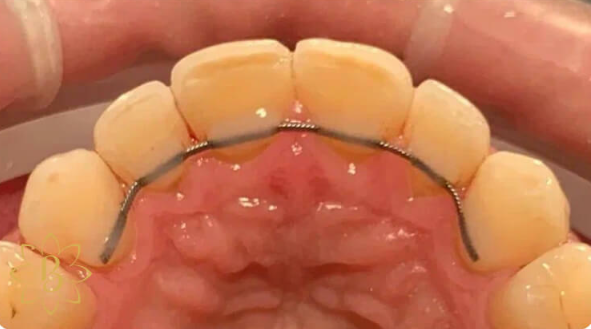

Профессиональная гигиена особенно важна при ортодонтическом лечении, ведь в повседневной жизни, дома, очень сложно поддерживать должный уровень гигиены полости рта! Даже если вы используете ирригатор и специальные ёршики! В нашей рубрике «до/после» вы видите то, что может быть с зубами при лечении брекетами, если не проводить своевременную чистку у врача-стоматолога. Марухно Дарья Александровна провела профессиональную чистку в несколько этапов, чтобы вернуть пациентке белизну ее собственных зубов! Брекет-система была поставлена не в нашей клинике, и почему пациентка не обратилась за профессиональной помощью раньше-вопрос) Но в данном случае, главное – итог! Кровоточивость после даже обычной чистки в такой клинической ситуации – естественный результат. Ведь обильный зубной налёт и зубной камень вызывают воспаление дёсен в виде гингивита, а порой даже пародонтита.

Доктор: Марухно Дарья Александровна